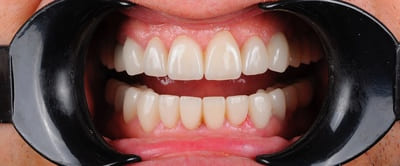

После

Неравномерная патологическая стираемость зубов. Установлены импланты в боковых отделах верху и внизу. Протезирование на имплантах циркониевыми коронками+ виниры на передние зубы.